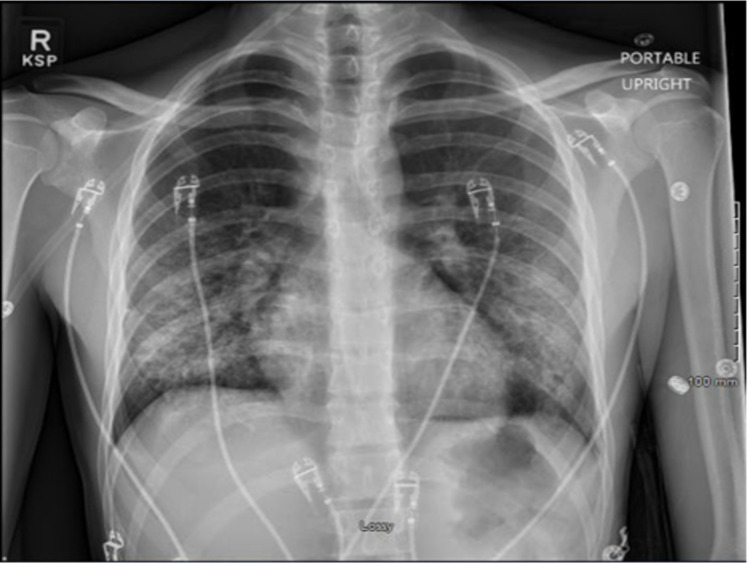

Infectious disease recommended discontinuing all antibiotics for low concern of infectious etiology. Pulmonology service recommended checking antinuclear antibodies (ANA), vasculitis panel with ANA, anti-glomerular basement membrane (anti-GBM) for initial eosinophilia. All these labs were negative, and eosinophilia was later resolved. He underwent bronchoscopy with bronchoalveolar lavage (BAL) and transbronchial biopsy. Infectious work-up on the BAL sample was unremarkable for viral, fungal, and bacterial pathogens and cytology demonstrated small clusters of atypical cells with a high nuclear to cytoplasmic ratio. The patient briefly required being on HFNC after bronchoscopy, but he was back on room air the third day after initiating methylprednisolone. Repeat CXR showed marked improvement in bilateral interstitial and soft tissue opacities (Figure 3).